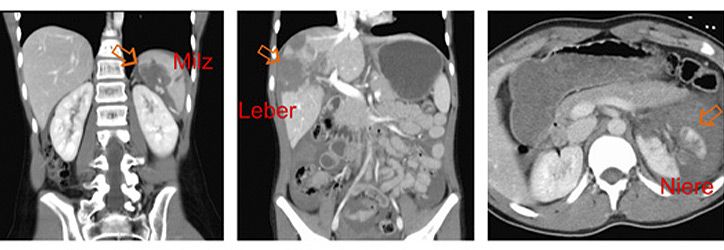

Verletzungen der Bauchorgane

Die Bauchorgane werden in Europa fast ausschließlich durch stumpfe Traumen verletzt. Die Unfallursachen sind altersabhängig und bei Kleinkindern v.a. Stürze, bei Schulkindern zunehmend Sportunfälle und in allen Altersgruppen Verkehrunfälle. Am häufigsten sind Milz, Leber und Nieren (Abbildung) verletzt, seltener die Bauchspeicheldrüse oder der Magen-Darm-Trakt.